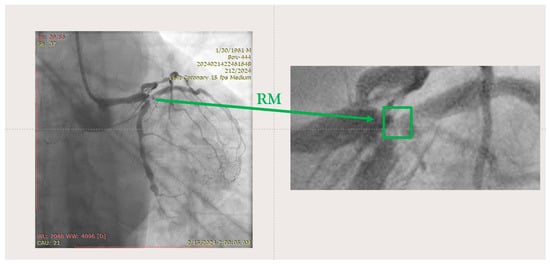

2. Case Presentation